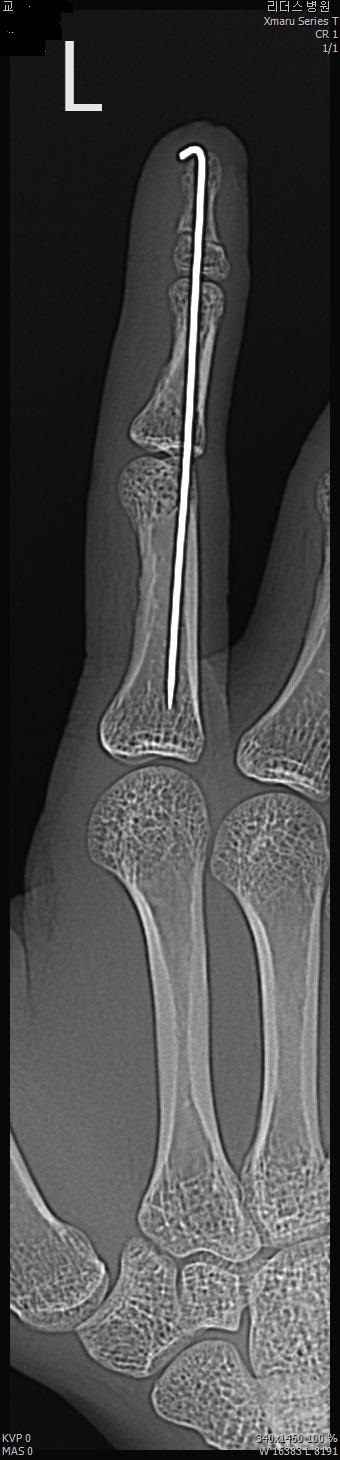

2017년 2월 14일 수지접합 ( 좌측 2수지 절단 치료 전, 후 모습)

2017년도 224일 당시 ( 외국인 교 **)께서 기계에 전달되어 본원 방문함.

올 해 19일 약 1년여간 수지접합 치료 전,후 과정을 올립니다.